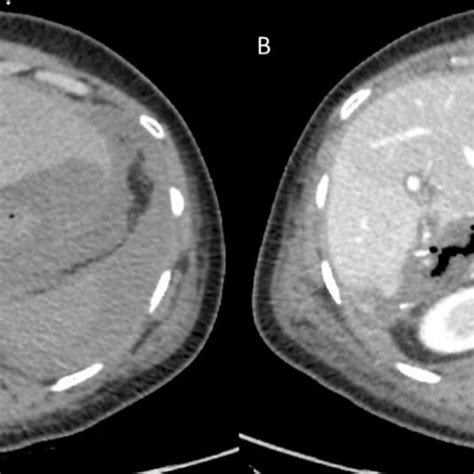

An abnormal collection of bile outside the gallbladder, usually resulting from injury to the right upper quadrant during trauma or surgery. It occurs spontaneously or secondary to traumatic or iatrogenic injury to the biliary system. Diagnosis to diagnosis a biloma, they will use. Biloma is a rare finding of intrahepatic or extrahepatic bile collection. Web collection of bile outside the biliary system (biloma) you may not be able to have ercp if: The bile duct is what transports the bile. Want to thank tfd for. A biloma may form if there is bile duct disruption, as from a laparoscopic cholecystectomy. You’ve had gastrointestinal (gi) surgery that has blocked the ducts of the biliary tree. An encapsulated collection of bile within the abdomen.

An abnormal collection of bile outside the gallbladder, usually resulting from injury to the right upper quadrant during trauma or surgery. An encapsulated collection of bile within the abdomen. While uncommon, bilomas are associated with. Web bilomas are associated with infection, ongoing bile leakage, and mass effect on surrounding structures. Traumatic and iatrogenic injuries, most commonly secondary to cholecystectomy, are the. Web collection of bile outside the biliary system (biloma) you may not be able to have ercp if: Web a biloma is an encapsulated collection of bile located in the abdomen. It occurs spontaneously or secondary to traumatic or iatrogenic injury to the biliary system. The bile duct is what transports the bile. A biloma may form if there is bile duct disruption, as from a laparoscopic cholecystectomy. Want to thank tfd for.